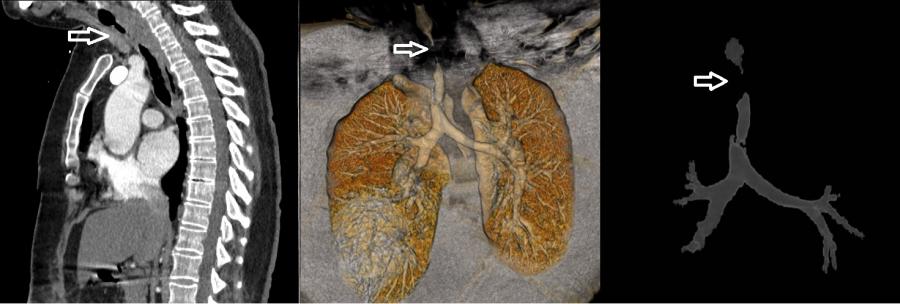

COVID-19 enfeksiyonu nedeniyle yoğun bakımda mekanik ventilatör ile tedavi görüp taburcu olan 52 yaşındaki kadın hasta, bir ay sonra nefes darlığı şikâyeti ile KTÜ Farabi Hastanesi Göğüs Cerrahisi Polikliniği’ne başvurdu. Yapılan detaylı tetkikler sonucunda hastanın soluk borusunda 4,5 cm uzunluğunda bir daralma tespit edildi. Solunum sisteminin en önemli unsurlarından birisi olan soluk borusunun hava yolunun açılması için acilen Rijit Bronkoskopi yöntemi uygulanarak hastanın soluk borusundaki darlık genişletildi. Hastanın solunumu geçici olarak rahatlatılarak sorunlu bölgenin detaylı olarak teşhis edilmesi sağlandı. Yapılan değerlendirmeler sonucunda, daralan soluk borusu kısmı için iki hafta sonrasına ameliyat planlandı.

Üniversitemiz Farabi Hastanesi Başhekimi Prof. Dr. Celal TEKİNBAŞ liderliğindeki ekip tarafından yapılan ameliyatta, hastanın soluk borusundaki daralmış kısım kesilip çıkarıldıktan sonra sağlıklı uçlar birbirine dikildi. Ameliyat sonrasında sadece 5 gün hastanede yatan hasta, sağlığına kavuşmasının ardından taburcu edildi. Sonraki süreçte, hastanın 10 günlük ve 2 aylık kontrollerinde hastada, hiçbir sorun olmadığı saptandı.